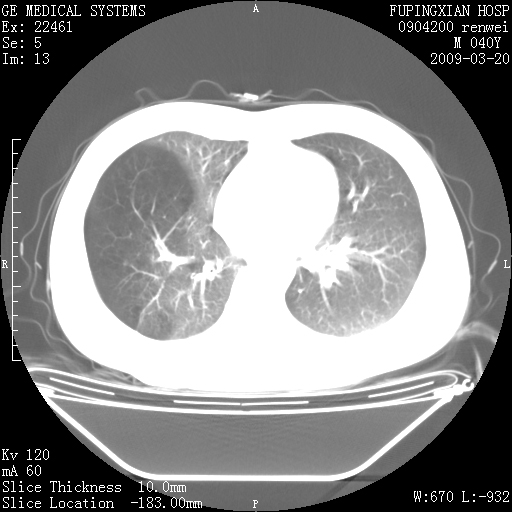

标题: CT18920:平时体健,体检时发现以下问题。

单侧肺气肿表现,原因?   特发性或先天性可能

右肺气肿。

右肺局限性肺气肿

右肺局限性肺气肿。

双肺弥漫磨玻样改变,肺纹理增重,考虑早期间质纤维化伴局部阻塞肺气肿,[考虑黏液栓]

右肺局限性肺气肿;[考虑黏液栓]所致。

双肺弥漫磨玻样改变,右肺局限性肺气肿。病人没有症状?

考虑间质性肺炎伴右侧局限性肺气肿,

先天性支气管闭锁

右肺局限性肺气肿,原因?先天支气管闭锁?粘液栓?